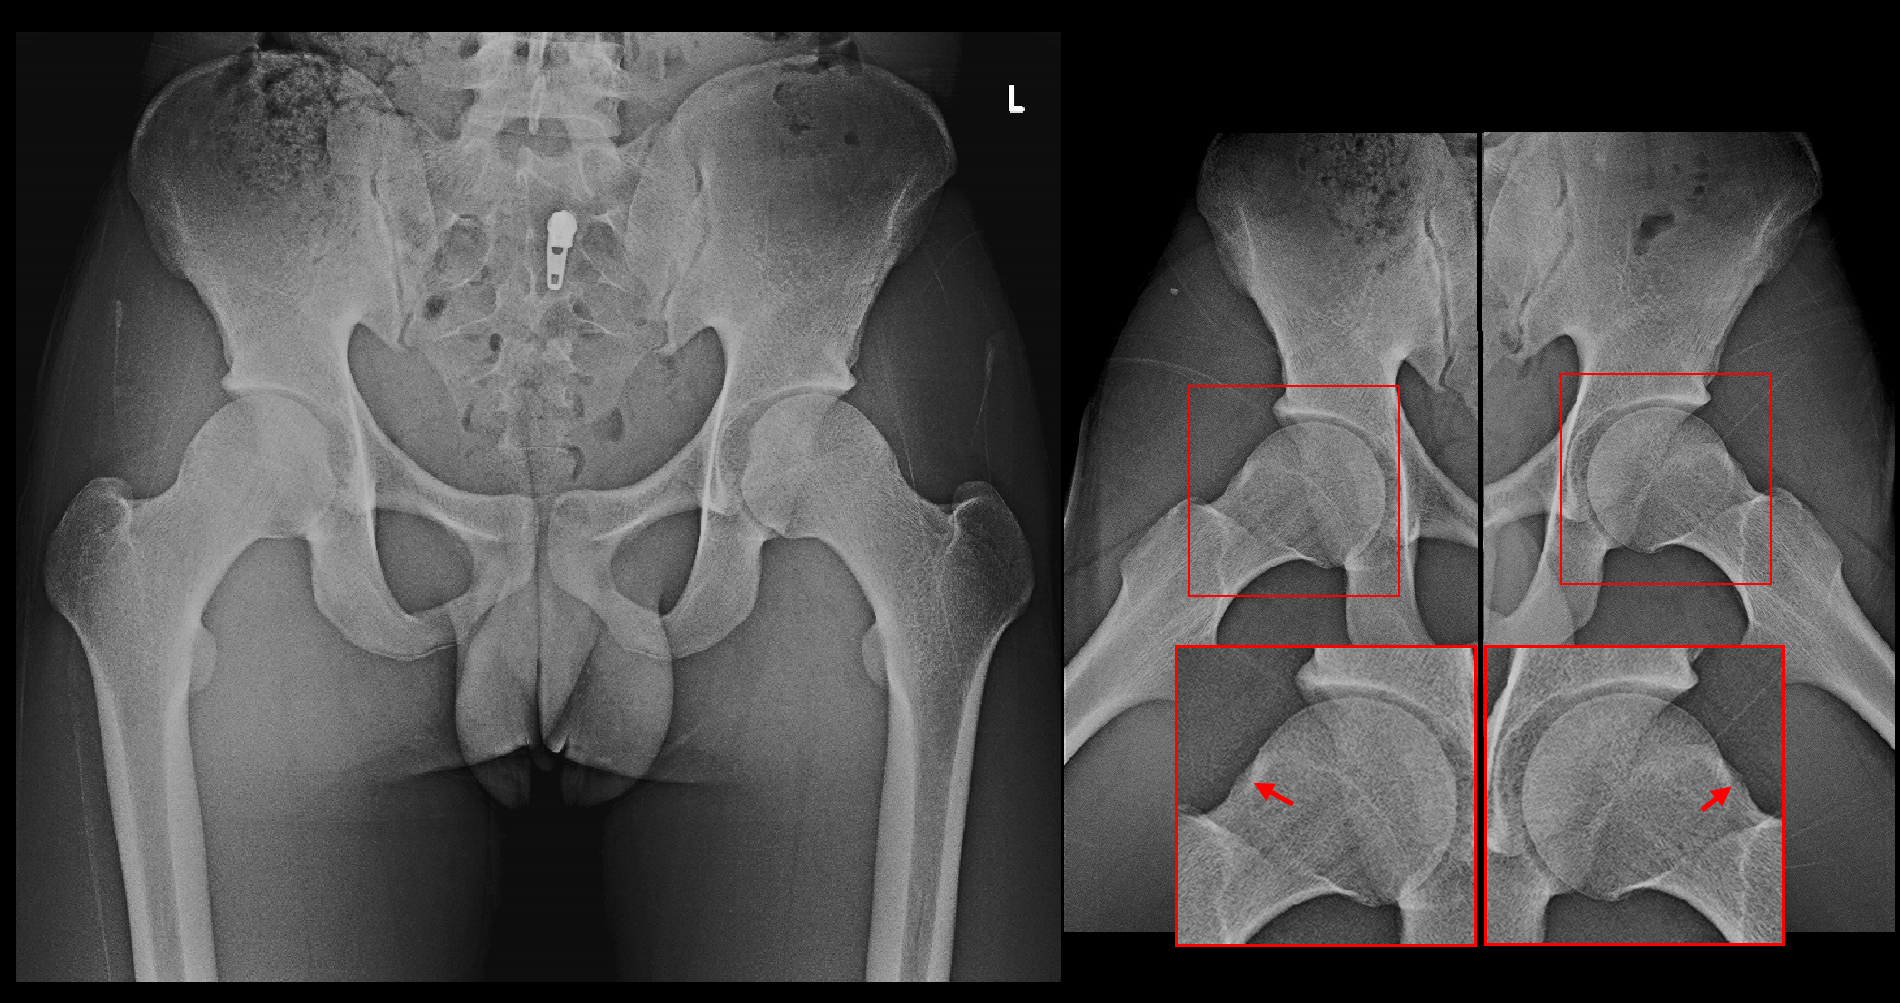

股関節は寛骨(解剖学的には腸骨・恥骨・坐骨という3つの骨が1つになった骨を寛骨と言います)と大腿骨から形成されており、大腿骨の頂上部は大腿骨頭と呼ばれ、その下のくびれた部分を大腿骨頚部(首)と表現します。大腿骨頭部がはまり込む骨盤(寛骨)側の陥凹部を臼蓋と呼ばれます。臼蓋部を取り囲むように赤く囲われた部分は関節唇という硬質ゴムのような軟骨となります。